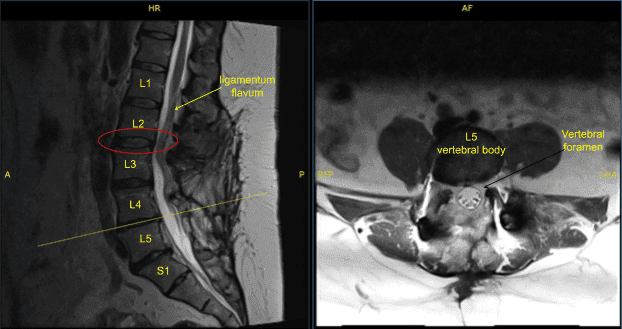

The patient was complaining of pain in both lower extremities. They had a history of L3 to S1 fusion done by another physician. Imaging studies showed good fusion mass from L3 to S1 but compression over L2-L3 segment with bilateral neural foraminal compression of L3 along with bony island formation over L3-L4 region with foraminal compression.

Disc bulge, facet osteoarthritis, buckling of ligamentum flavum

Status post posterior decompression the spinal canal from L2 through S1